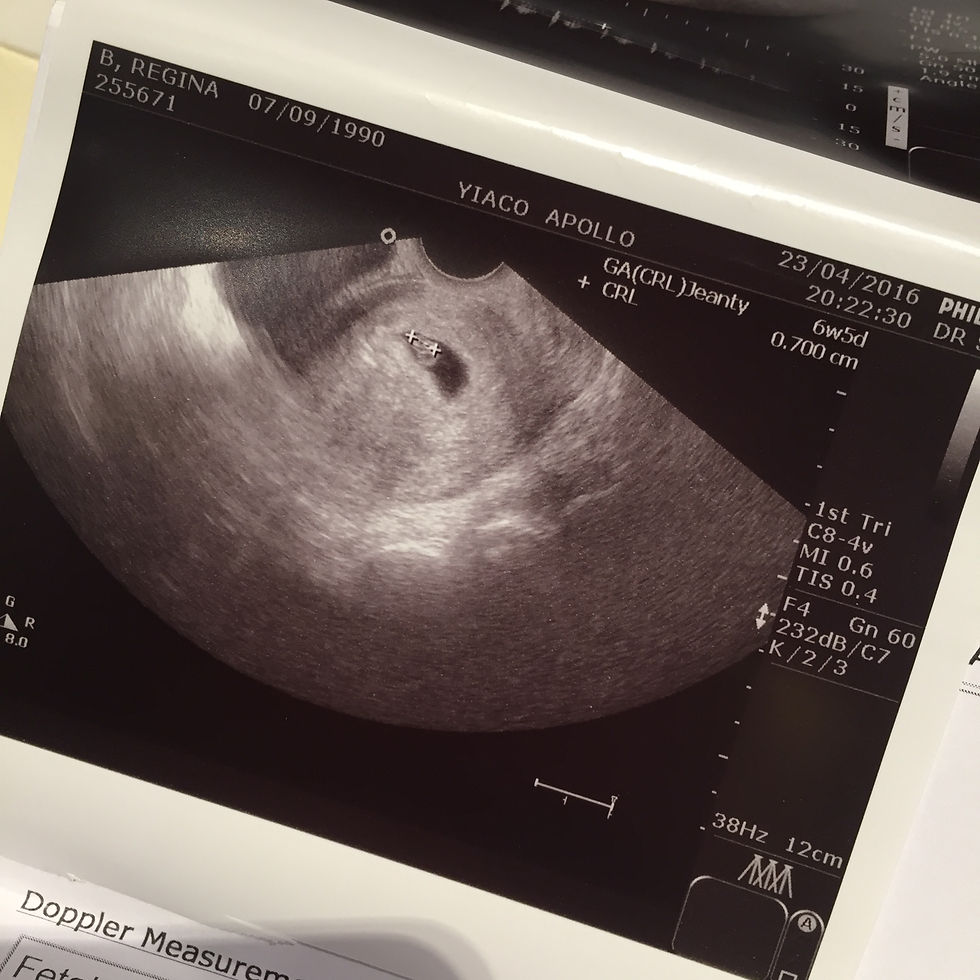

We had our first check up that week and little did I know that my heart would be moved so much that day. It was like meeting a very special person for the first time. When the ob did the ultrasound and I heard the swooshing heartbeat of the little sweetpea inside me, I cried. I felt an enormous joy knowing that there is life in my womb and that life is a gift.

The scan photo showed a still very small embryo but I already felt a very big love for him/her. ♥

Hello there, daddy calls you his little dinosaur ♥